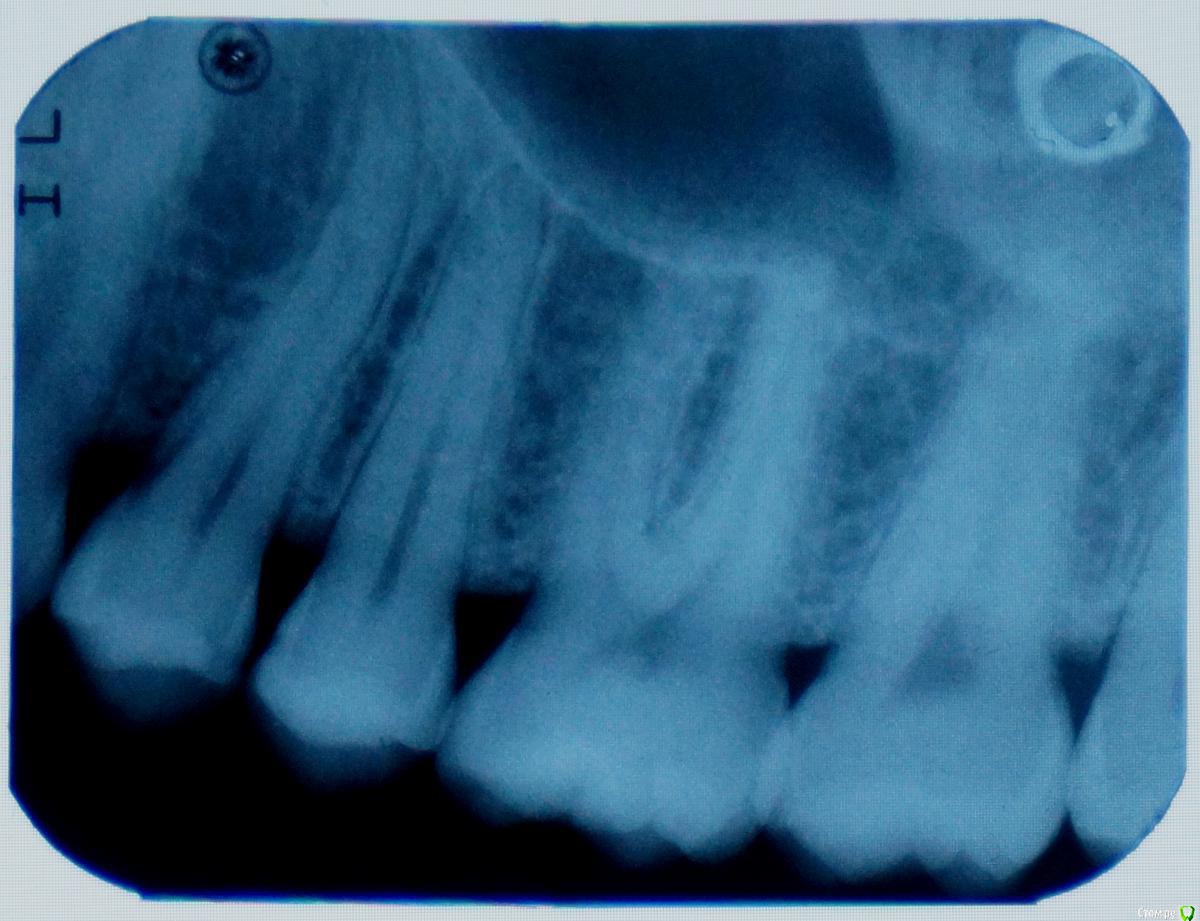

Манул Опубликовано 10 сентября, 2015 Поделиться Опубликовано 10 сентября, 2015 Здравствуйте. У меня боль в суставе челюстном слева, глаз отекает (мешок с утра). И при жевании боль в 6 зубе верхнем слева (если считать от центрального резца). Сделал панорамный, на нем всё нормально? Что делать, что может быть? Спасибо. Ссылка на комментарий

krokomot Опубликовано 10 сентября, 2015 Поделиться Опубликовано 10 сентября, 2015 По вашему снимку видимой патологии не наблюдается, нужно обратиться непосредственно на прием, если беспокоят зубы проверить их на витальность. Это все можно сделать только в клинике форум вам тут не поможет все будет только пальцем в небо. Ссылка на комментарий

Манул Опубликовано 11 сентября, 2015 Автор Поделиться Опубликовано 11 сентября, 2015 По вашему снимку видимой патологии не наблюдается, нужно обратиться непосредственно на прием, если беспокоят зубы проверить их на витальность. Это все можно сделать только в клинике форум вам тут не поможет все будет только пальцем в небо.Проблема в том, что зубы все интактны (стучали и воздушной струей проверяли), я у многих врачей был у 3 хирургов, 5 парадонтологов, 2 терапевтов..."У вас всё в норме!"А боль не проходит, есть не могу и глаз отекает (как фингал под глазом небольшой).Окулист сказа его патологии нет, у ЛОРа пока не был, но заложенности носа нет...Я не знаю что делать, всё в норме, а всё болит. Я не могу сказать, что идет усиление боли со временем, но и не проходит ничего. Ссылка на комментарий

Манул Опубликовано 22 сентября, 2015 Автор Поделиться Опубликовано 22 сентября, 2015 Спасибо всем огромное! По зависящим от меня причинам, я вынужденно исчез. С вычислительной техникой проблемы случились...На зубах кариес межзубной начался на стороне где болело. (между пятым, шестым и четвертым зубами)Подскажите стоит пломбировать или подожать нужно.Пишу с Raspberry pi b model 1... ((( Спасибо! Ссылка на комментарий